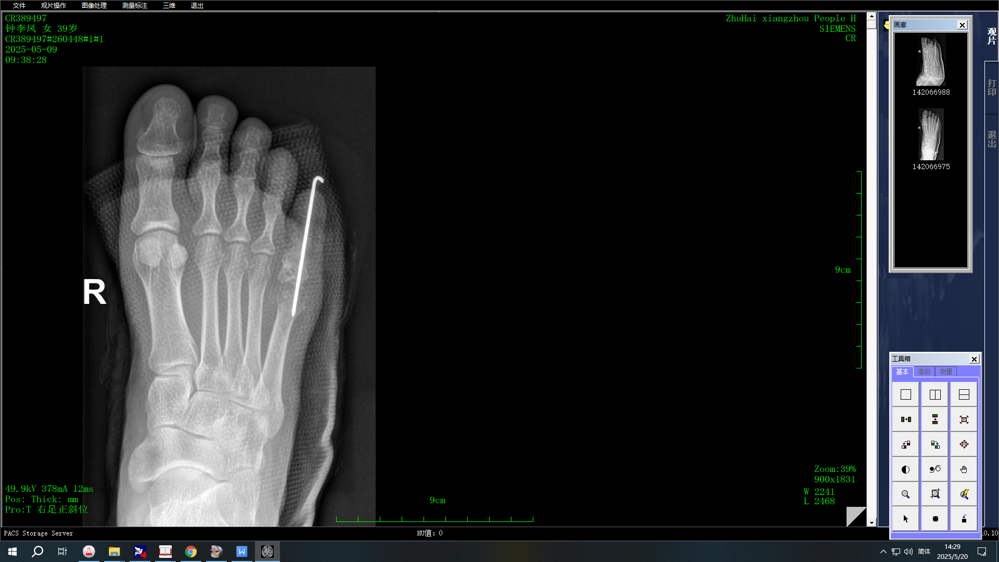

术后影像学检查

该例患者因病理性骨折,手术指征明确。完善相关检查后,pilipili 骨科团队为其进行了足趾病灶清除、取髂骨植骨及骨折复位内固定术。术后患者恢复良好,伤口稳定,症状得到缓解,已顺利出院。